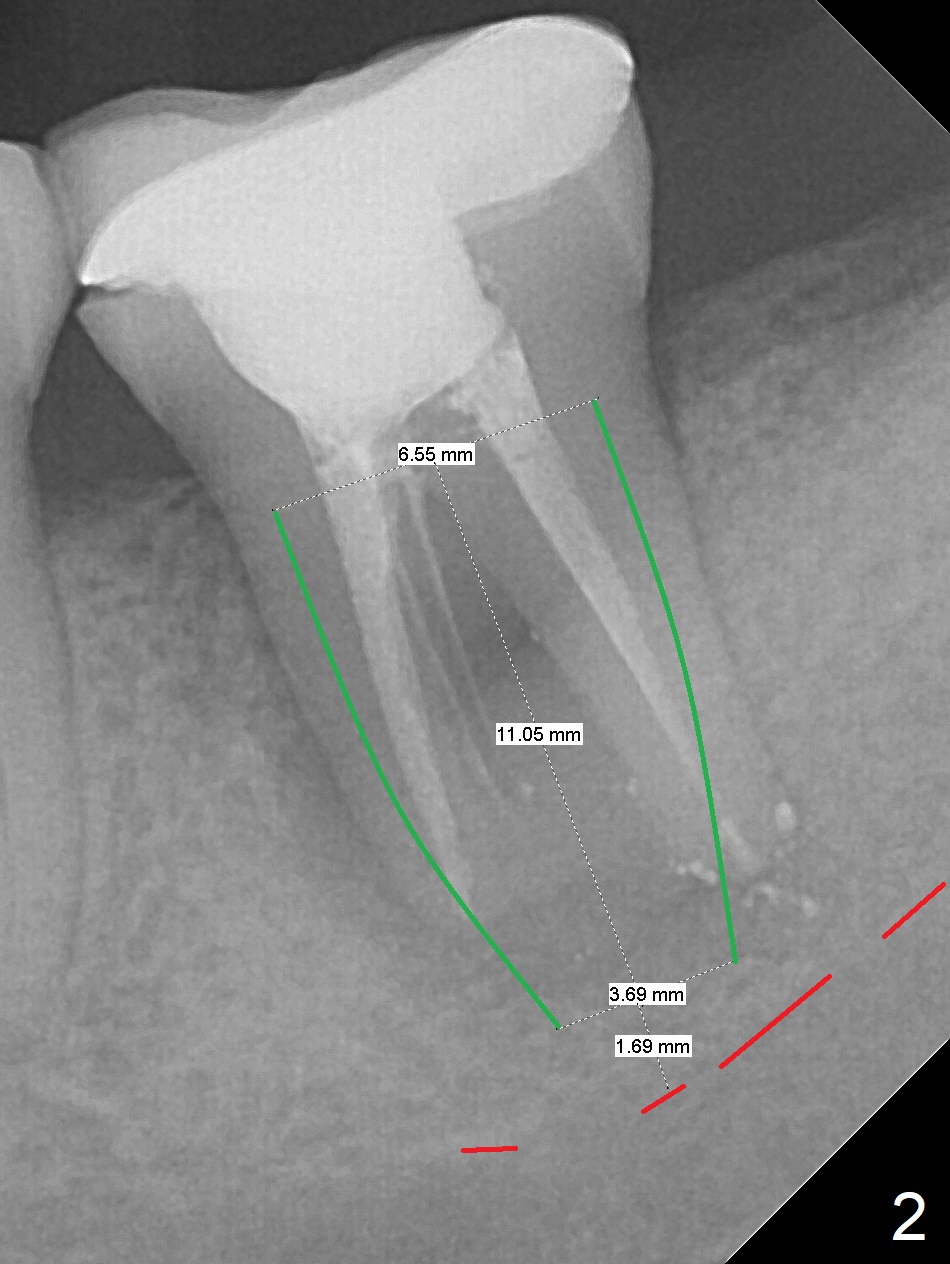

Six months post cementation of #30 implant crown, the 40-year-old woman (CY) returns with chief complaint of lower left abscess. The buccal furca at #18 has inflamed tissue with large radiolucency (Fig.1 *). To avoid the Inferior Alveolar Canal (Fig.2 red dashed line), use taps (most likely starting with 5 mm one) and dummy implants to form osteotomy after extraction and granulation tissue removal. The definitive implant is expected to be 6.5x11 mm. Switch to Tatum implants if the largest IBS is unable to achieve primary stability.